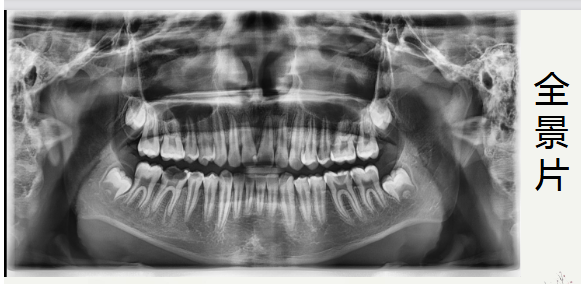

右下第一磨牙颌面大面积坏,可探及腔,叩+,无松动,无冷热刺激敏感。辅助检查:X线片显示左下第一磨牙远中邻面阴影,颌面阴影近腔,根尖口闭合,根尖无明显暗影。右下第一磨牙颌面大面积缺损,顶呈半散开状,根尖区闭合,伴根尖暗影。诊断:左下第一磨牙:急性牙髓炎

通过术前照与X线片,小牙片可见,颌面龋坏,远中邻面龋坏,叩+,松动-,